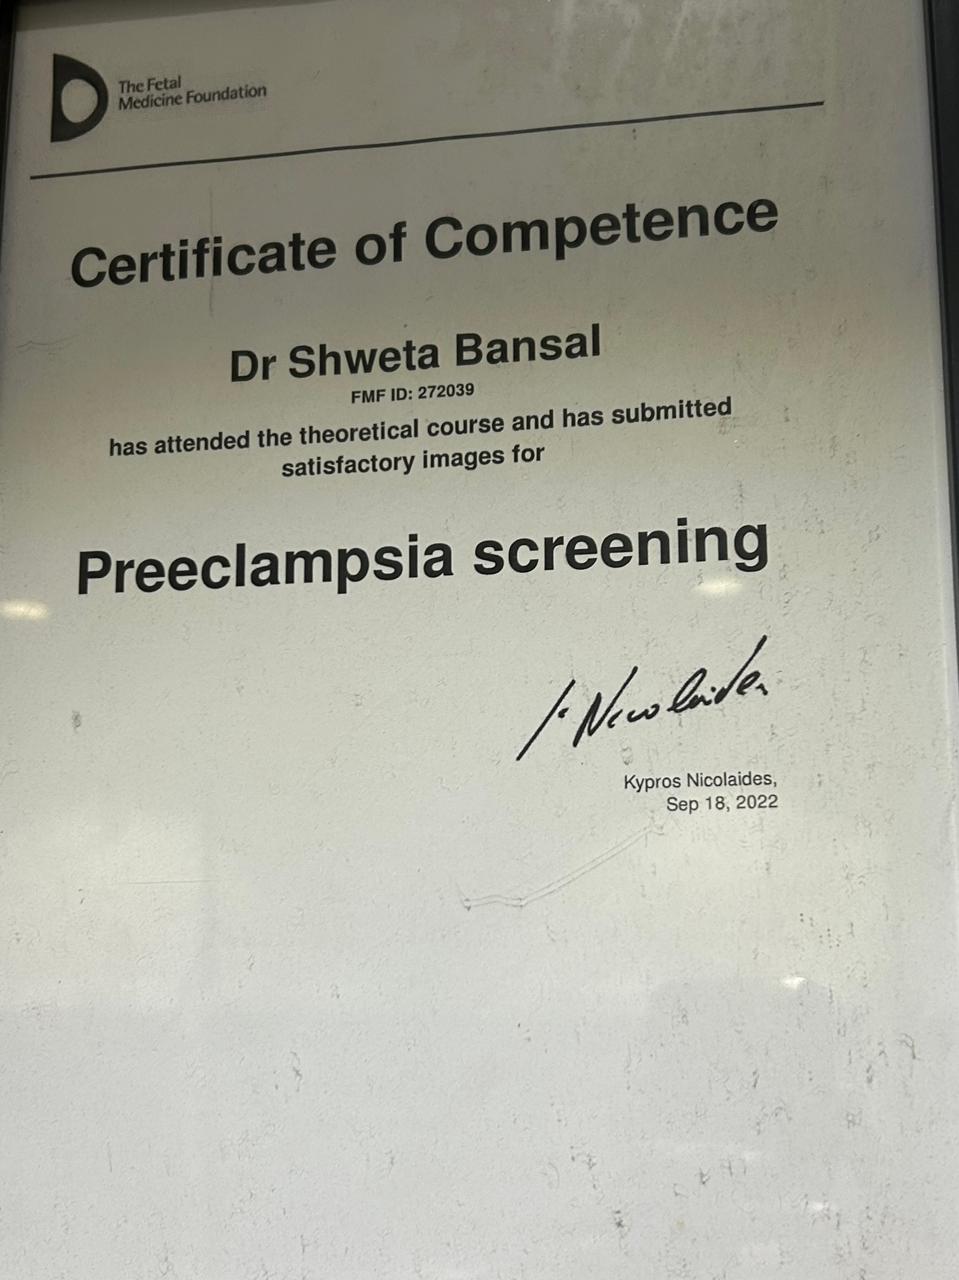

Dr. Shweta Diagnostic & Child Care Centre

Expert Care in Fetal Medicine, Pediatrics & Diagnostics